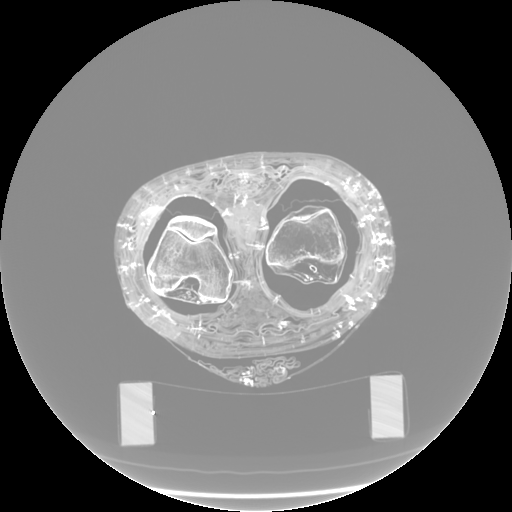

Figure 3: Visualization of axial frames of a mummy [6] selected in proximity of the thigh. (a) Some of the regions we are interested to segment are indicated. (b) Artifacts caused by presence of metals.

In Fig. 3a, we show one axial slice of a male mummy with indication of the regions to be segmented. Fig. 3b illustrates that metals present inside a bandaged mummy generate severe artifacts, which are not present in standard biomedical data.